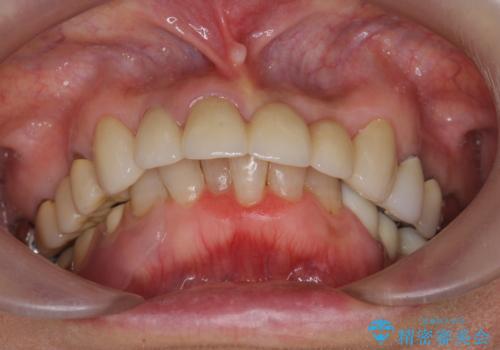

抜歯後の見た目改善として深い咬合関係であることからインプラントは避け、ブリッジで補綴治療を行っていくこととしました。

- 72.6万円(仮歯・ジルコニアクラウン×6)費用は治療当時の料金となります

元々の噛み合わせが深く(ディープバイト)、転んで顎を強打したことで上顎前歯2本が根元から折れてしまい抜歯をしなければいけない状況となってしまいました。

今後前歯への負担を減らすためにナイトガードマウスピースを使用していただき歯の保存に努めていきます。